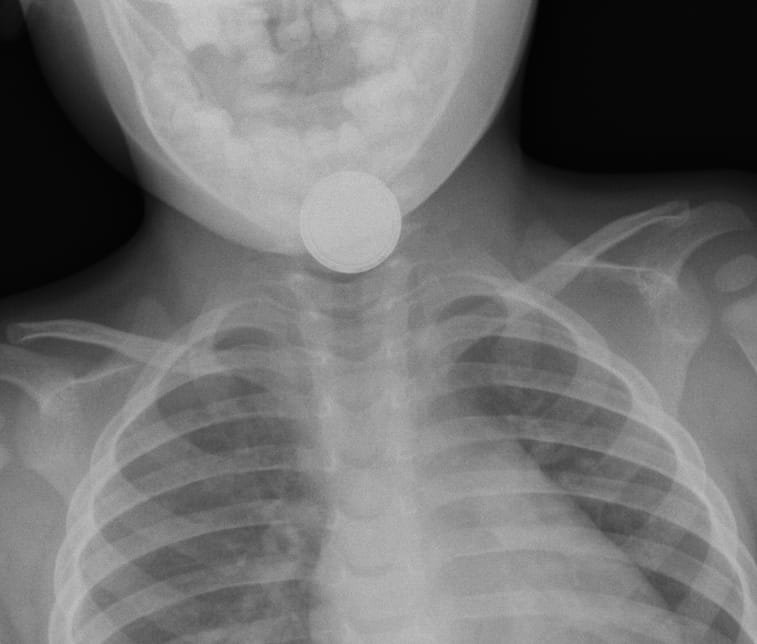

תמונת רנטגן של הסוללה שנבלעה.

קרדיט לצילום: דוברות מרכז שניידר.

התינוק הובהל למרכז שניידר לרפואת ילדים, שם בחדר הניתוח, שלפו מומחי מערך א.א.ג, המכון לגסטרואנטרולוגיה, וצוות חדר הניתוח המיומן, את הסוללה העגולה מהוושט של התינוק הקטן והוא הועבר להתאוששות ביחידה לטיפול נמרץ בשניידר.

כאמור, עד שהגיע התינוק לקבלת טיפול רפואי, כבר החלו החומרים המצויים בסוללה להתפרק בגוף וגרמו לנקב בוושט של התינוק הקטן. בנוסף, הנזק היה נרחב והגיע עד מילימטרים ספורים מאבי העורקים של התינוק.